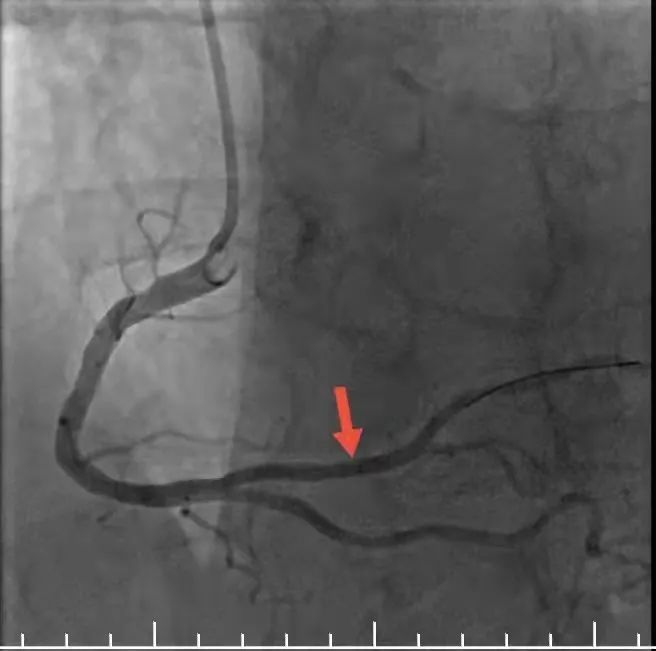

支架植入后,狭窄血管开通

在医院心内科和导管室医护人员全力配合下,短短半小时医生便完成手术,为肖恩顺利植入心脏支架,成功开通病变血管。